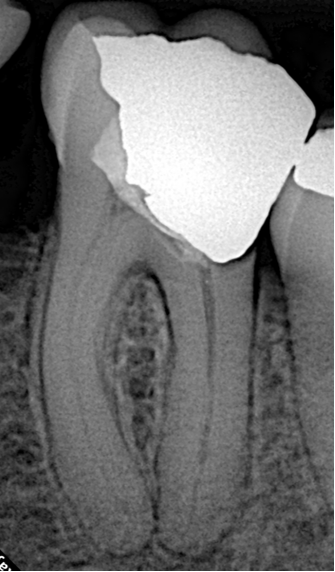

Pre-operative radiograph revealed a previous inadequate pulpotomy treatment and confirmed the unusual canal length, making this a technically demanding case.

- Diagnosis: Previously treated with Pulpotec, poor proximal contact with the second molar, and symptomatic irreversible pulpitis / apical periodontitis